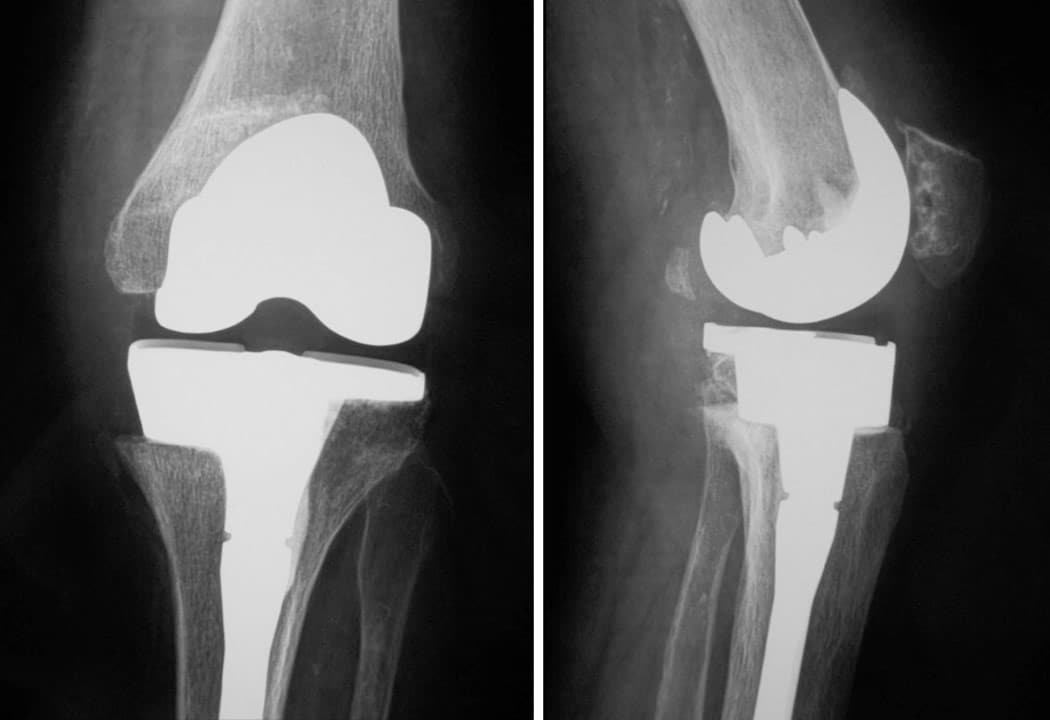

Douleur + raideur + boiterie. Homme 75 ans, opéré du ligament croisé antérieur 40 ans auparavant. On propose une prothèse totale du genou. Rééducation immédiate, récupération en 4 mois sauf complication.

Prothèse totale du genou NexGen (société Zimmer) à glissement, cimentée au fémur, au tibia et à la rotule, plateau polyéthylène fixe, postéro-stabilisée.